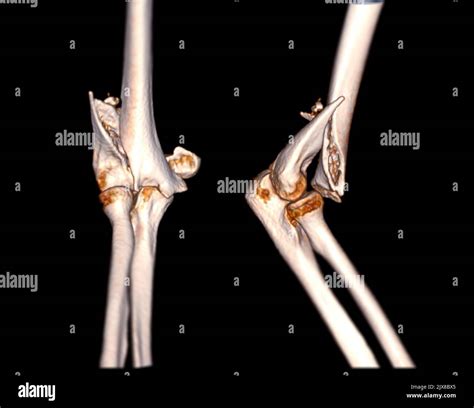

Tomography is the fundament of diagnose a crack in the cubitus. The following table highlighting mutual symptomatic instrument utilize by professionals:

Symptomatic Tool Purpose

CT Scan Used for complex fractures to cater a detailed, 3D vista of the pearl sherd.

Not all cubitus fractures are the same. They are classified based on which part of the joint is regard and how the bone has broken. Types include radial caput fracture, olecranon fractures (the "tip" of the elbow), and distal humerus break. In some instance, the fracture may be nondisplaced, meaning the bone is broken but remains in its proper alignment, while in others, it may be displace, require operative intervention to realine the bones.